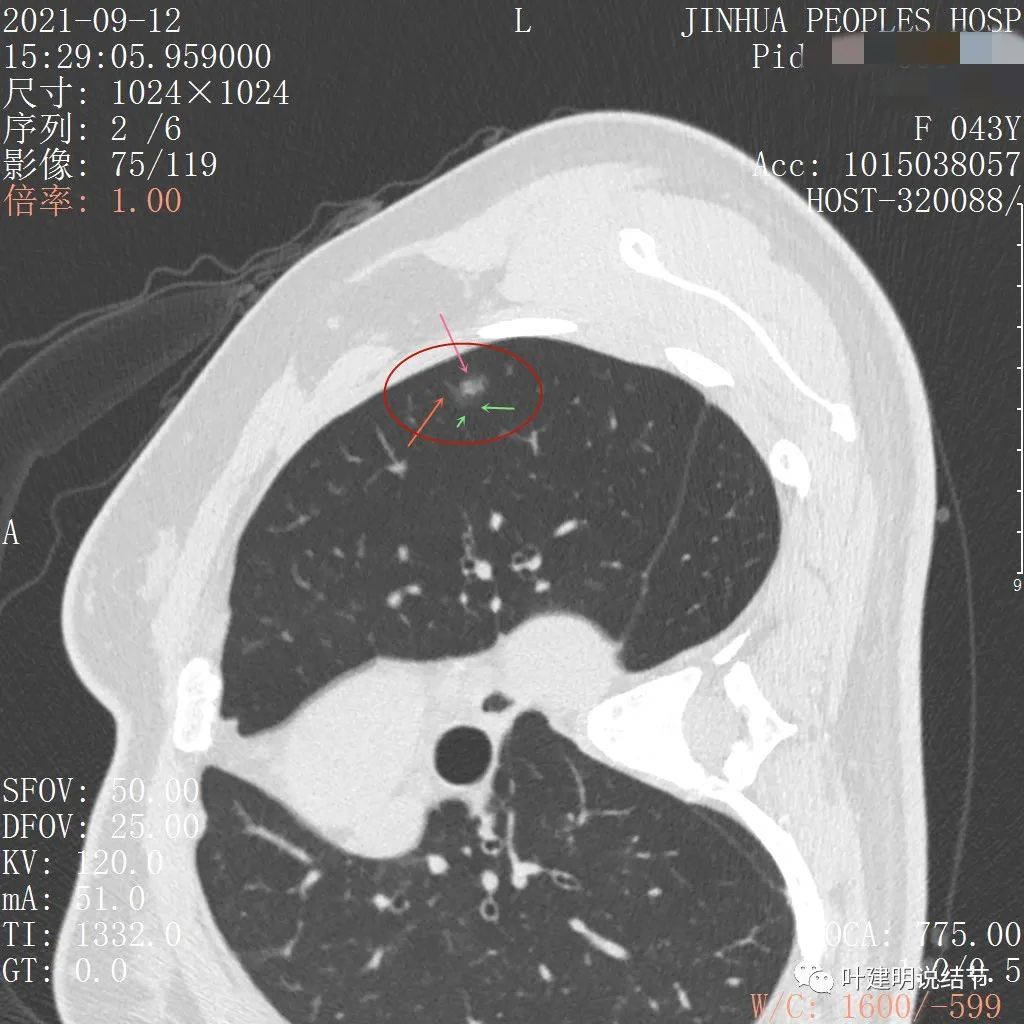

病灶整体密度较低,但轮廓较清,内部密度不大均匀,显得杂乱

不均质的偏低密度磨玻璃结节,轮廓清

上图示病灶内部有高密度点状成分(粉色箭头所指)

同样示内部点状高密度,瘤肺边界清,密度显乱

上图显示混合磨玻璃结节,中间点状高密度区域,边上有微小血管征

上图示病灶边缘磨玻璃成分有的区域密度过低(绿色箭头),事后回头来看,磨玻璃部分的密度过低,不容易是浸润性腺癌,而更符合原位腺癌